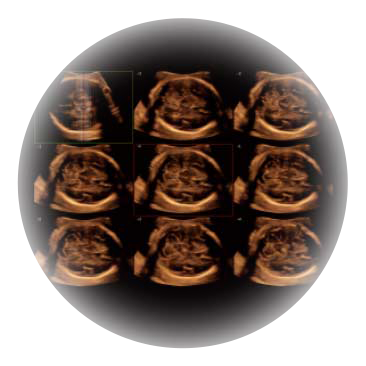

• M-Slice多切面成像

0.5mm厚度的薄层切片显像,可清晰显示微小病灶的连续断面。

• S-Live Silhouette光影成像

可同时显示组织结构表面和内部的轮廓信息,达到透视效果,为临床提供更丰富的诊断信息。

临床图